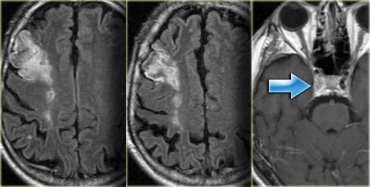

Image on left is SWI

Image on right is DWI

Stroke Syndrome:

In a right-handed patient:

Right superior division MCA